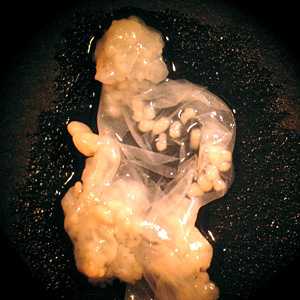

Gross coenurus specimens.

Coenurosis is infection by the metacestode larval stage (coenurus) of Taenia multiceps and T. serialis. Coenuri may be found in most tissue types, but those of T. multiceps have a predilection for the central nervous system and eye; those of T. serialis are usually found in subcutaneous tissue. Coenuri are thin-walled, whitish or gray, and spherical to polycephalic in shape. A coenurus contains multiple protoscoleces, which distinguishes it from a cysticercus, which contains a single protoscolex. Also, the length of the large hooklets on the protoscoleces can be useful in separating cysticerci from coenuri: the long hooklets of a metacestode of T. serialis and T. multiceps measure 110-175 µm long; those of T. solium measure 100-130 µm long.

Figure A

Figure A: Large, polycephalic coenurus removed from the shoulder of a baboon (Papio sp.).

Figure B

Figure B: Close-up of a coenurus of T. multiceps removed from the eye of a patient, broken open to show multiple protoscoleces.